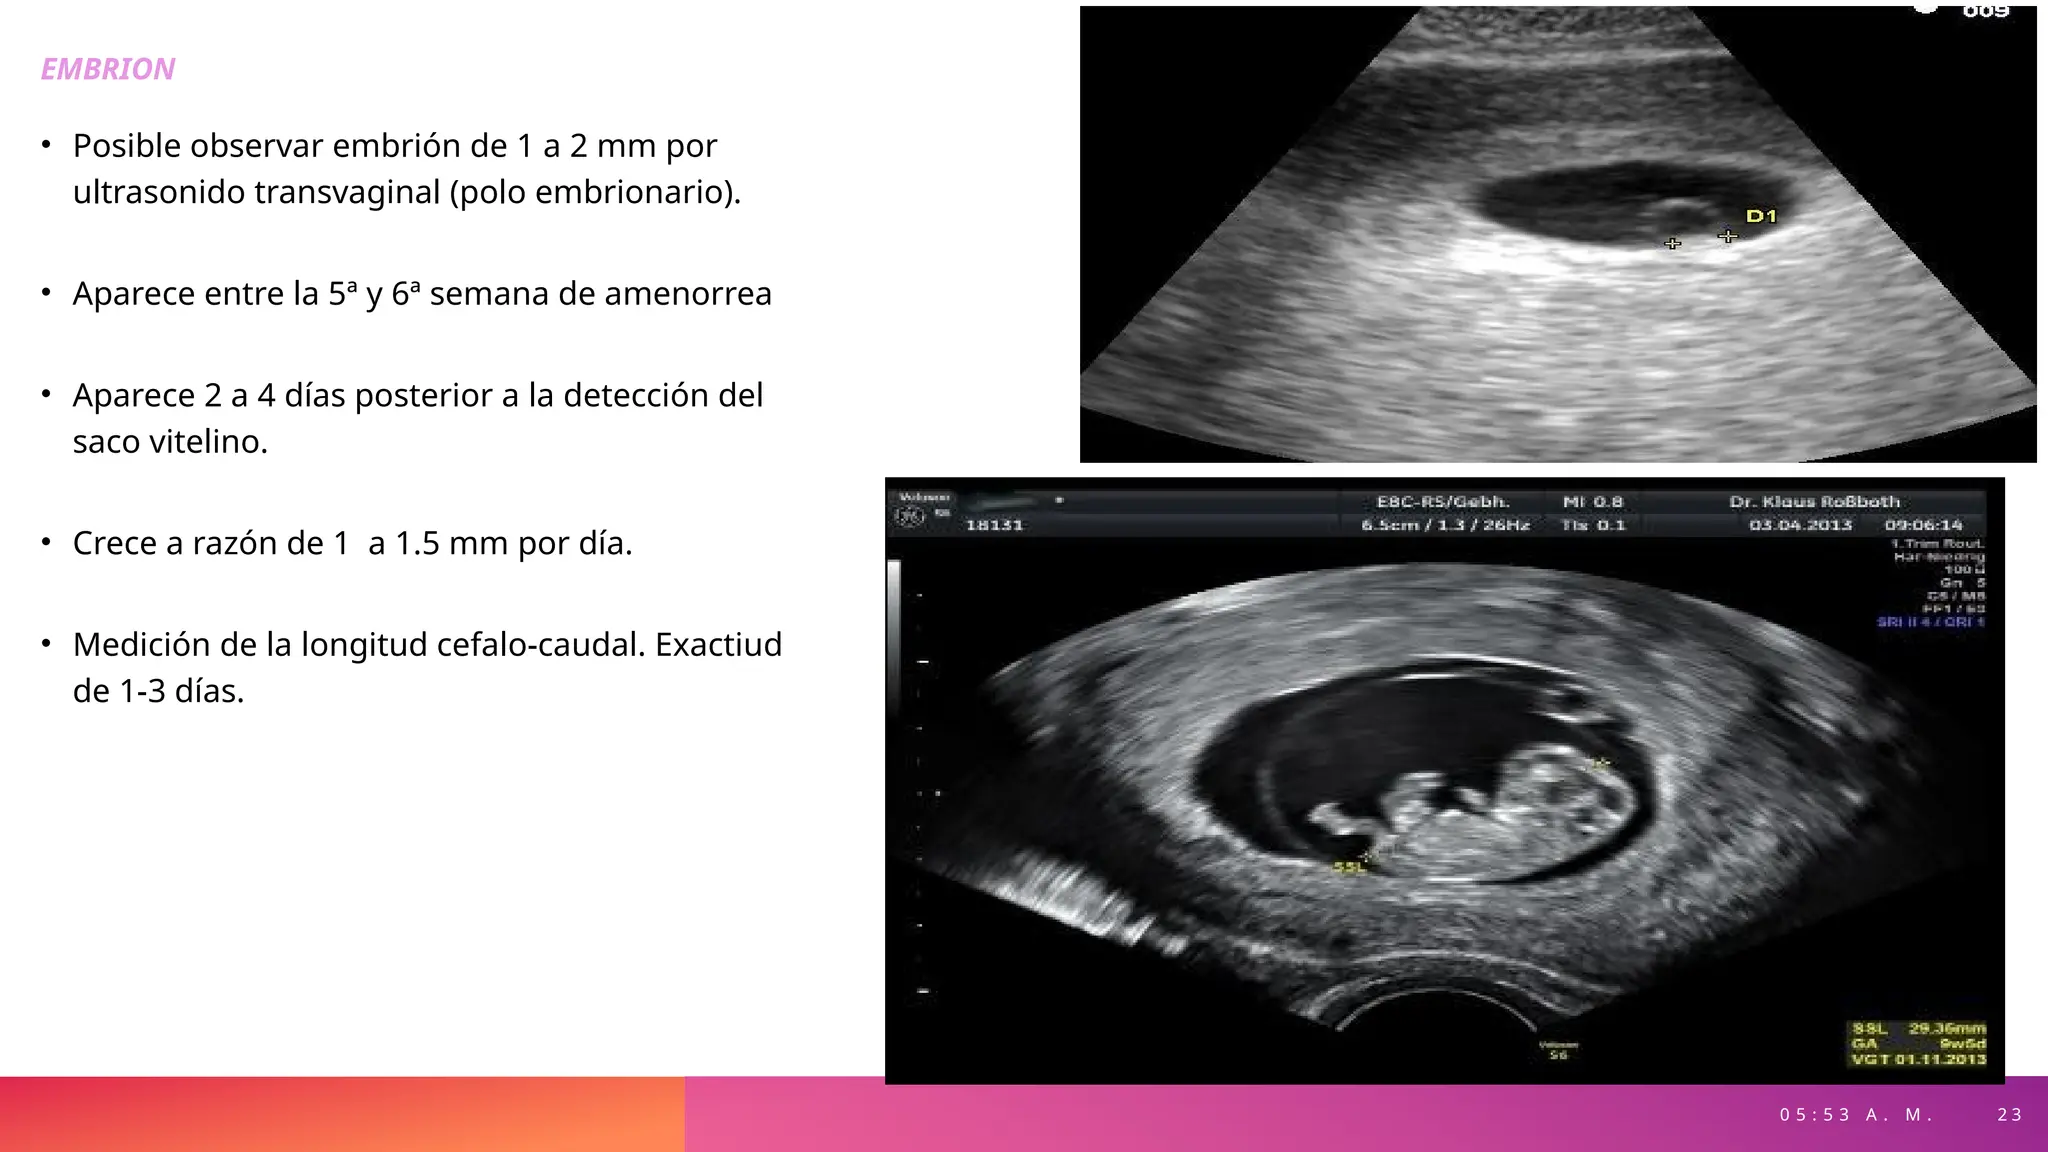

EMBRION

• Posible observar embrión de 1 a 2 mm por

ultrasonido transvaginal (polo embrionario).

• Aparece entre la 5ª y 6ª semana de amenorrea

• Aparece 2 a 4 días posterior a la detección del

saco vitelino.

• Crece a razón de 1 a 1.5 mm por día.

• Medición de la longitud cefalo-caudal. Exactiud

de 1-3 días.